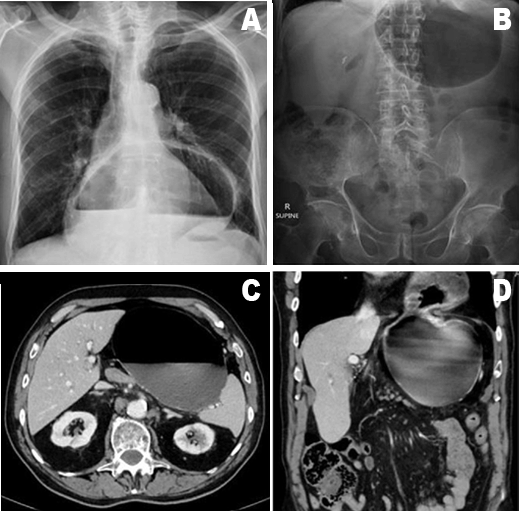

Upon presentation, the patient was hemodynamically stable and examination was unremarkable with a soft, non-peritonitic abdomen and no significant findings. Initial abdominal and chest X-ray revealed a large hiatus hernia and follow-up computed tomography scan of abdomen confirmed the presence of a large, Type III gastric volvulus (Figure 1).

Figure 1: (A–D) Radiological (X-rays and computed tomography scan) confirmation of large hiatal hernia with volvulus which has resulted in the pars media and antrum passing through the esophageal hiatus into the stomach.